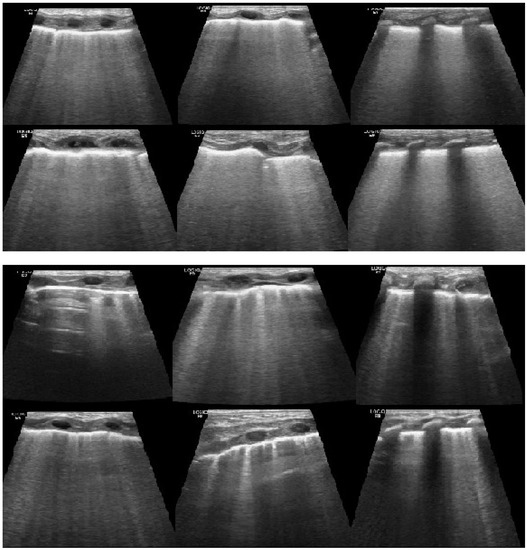

3. Results